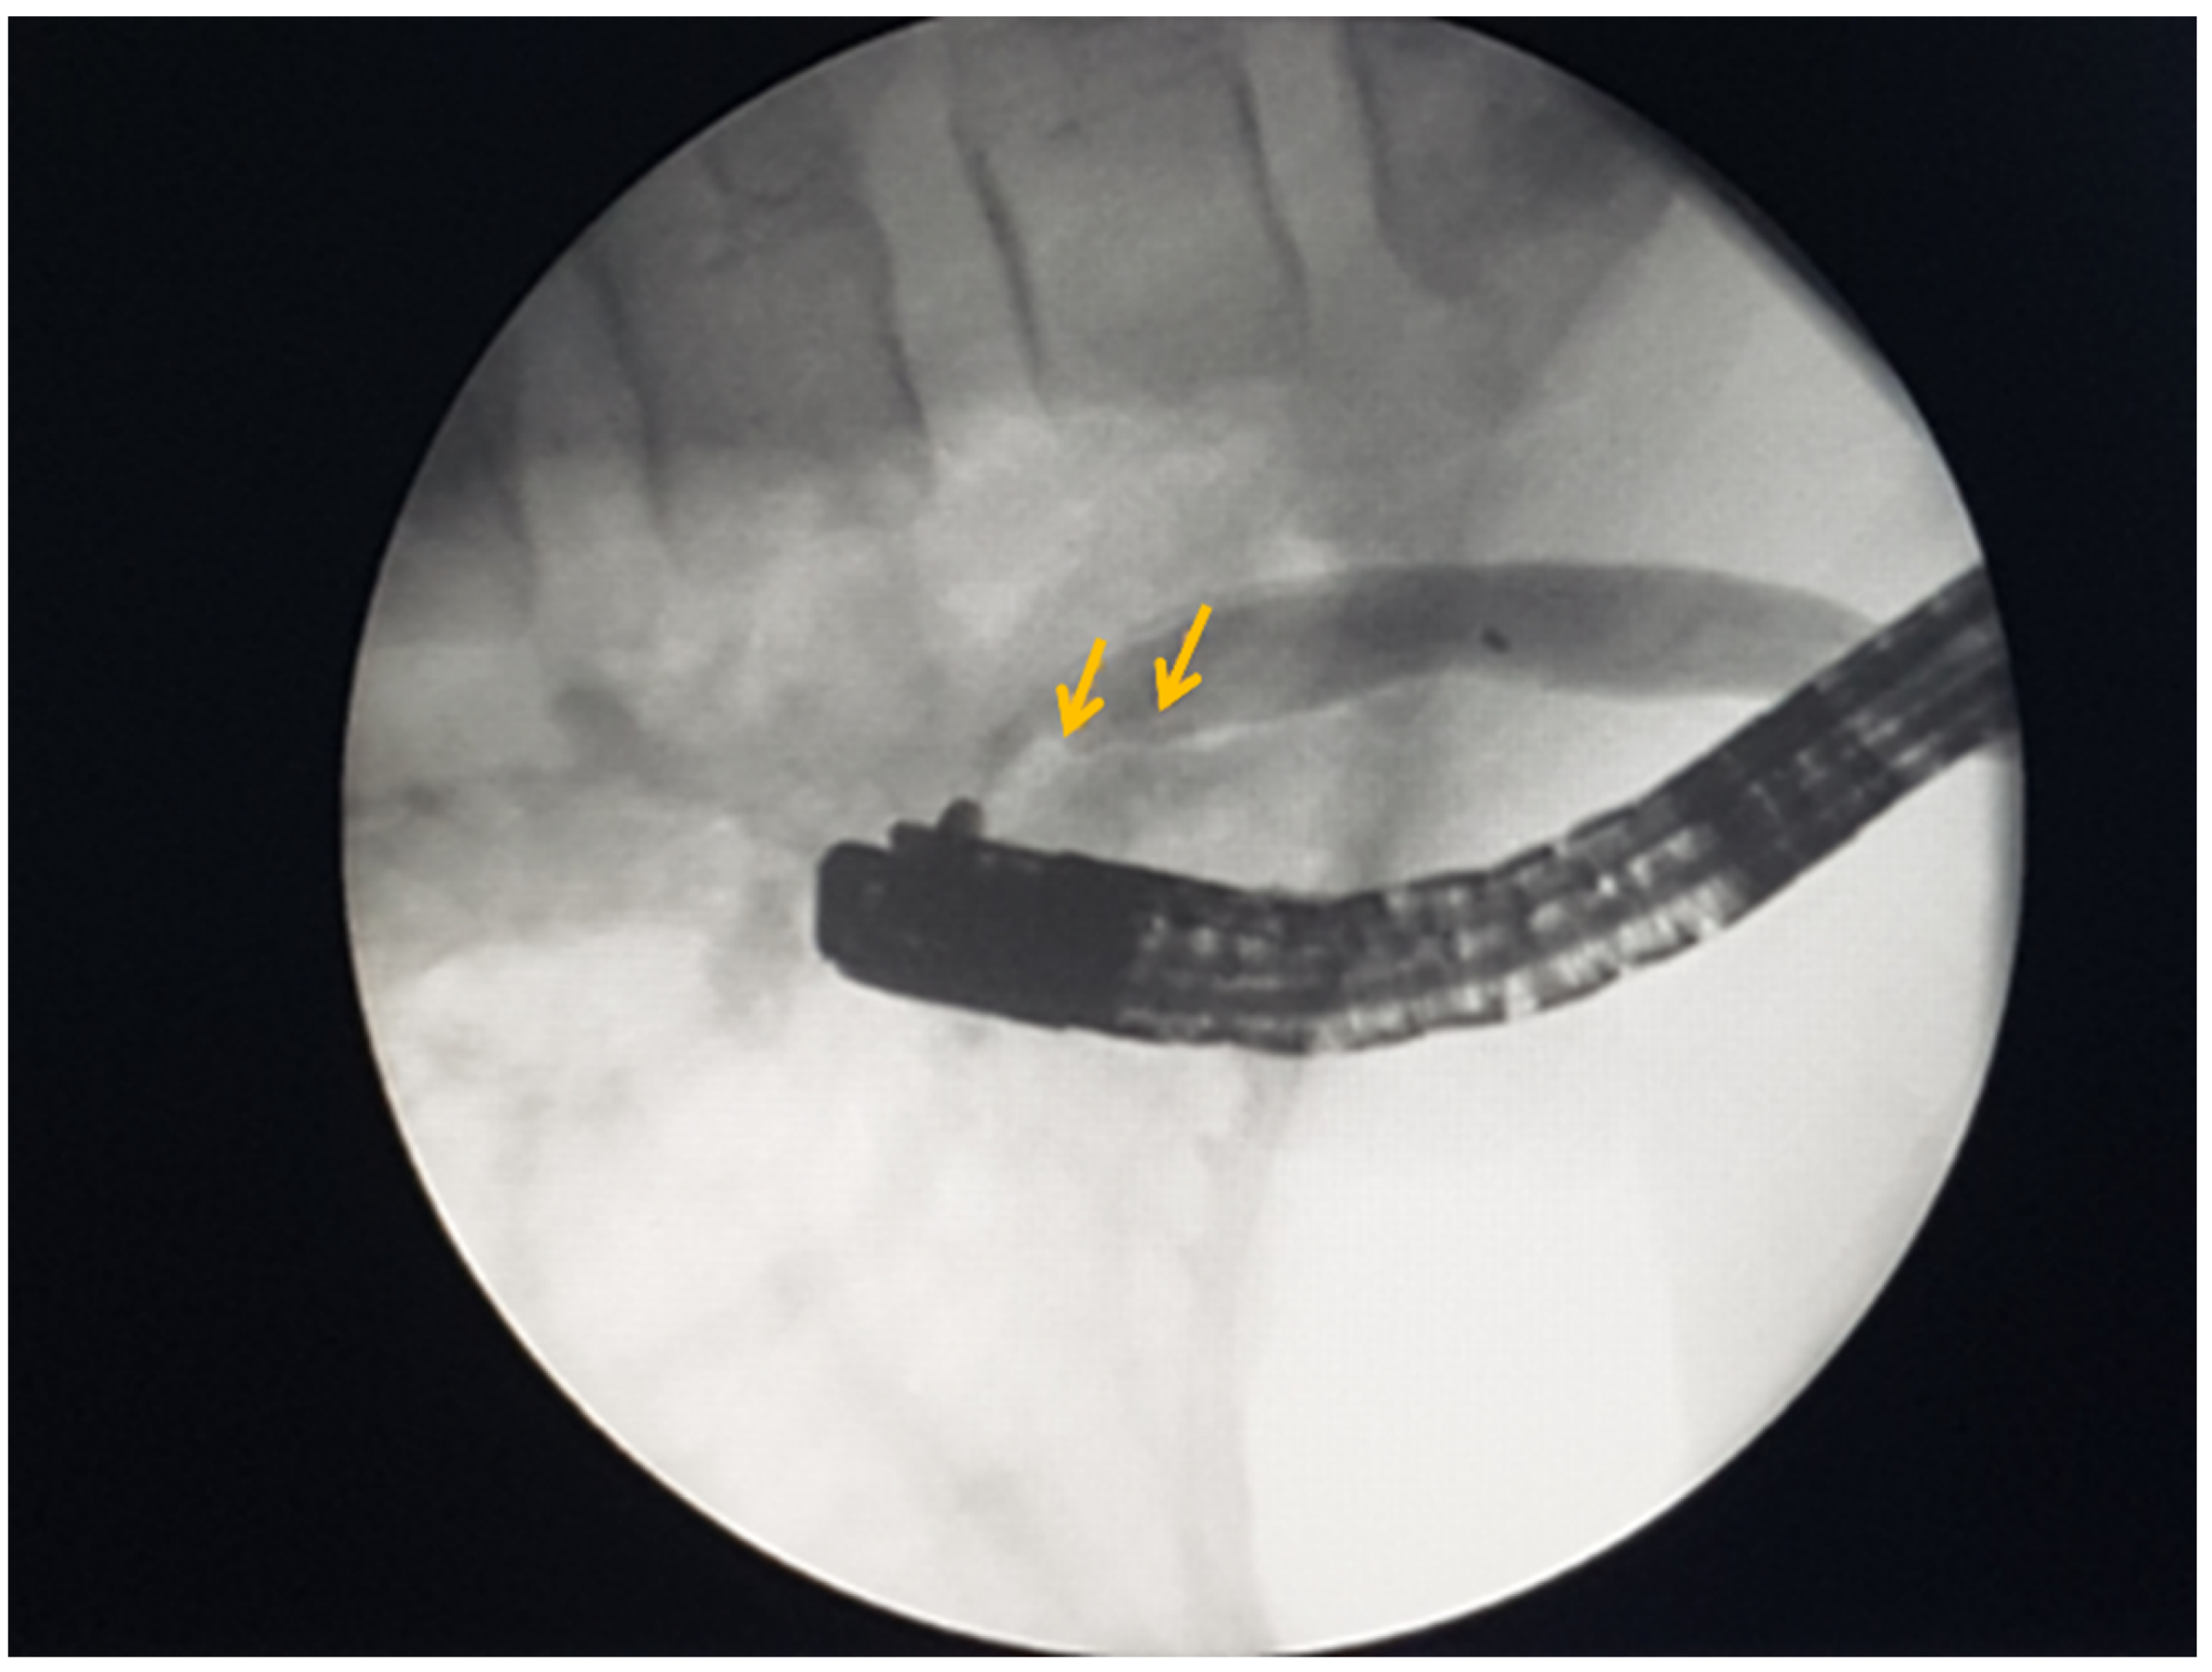

Mebendazole was administered to the patient three days prior to her undergoing endoscopic retrograde cholangiopancreatography (ERCP). The ERCP demonstrated an elongated, endemic p. Vateri crease with a dilated sphincter and bloody bile. Biliary cannulation was unsuccessful. For this reason, a precut sphincterotomy was performed and deep CBD cannulation was repeated. Further, contrast material was injected, and a dilation with filling defects was detected (Figure 3).

To preserve the integrity of the sphincter, a balloon dilatation of the CBD hiatus was performed with a 6 mm balloon, and CBD was revised. By using an extraction balloon, a few turbidities with black-colored inclusions were extracted, and the extracted material was determined to be the likely remains of an A. lumbricoides individual.

Figure 3. ERCP: CBD filling defects (yellow arrows).